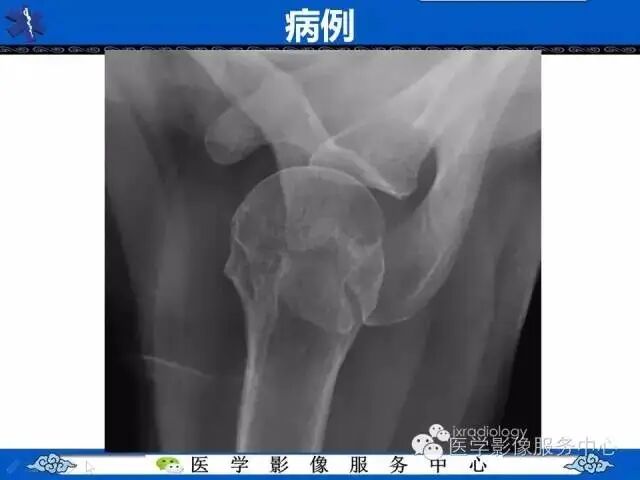

上述病例所示,肩峰处骨皮质不连续、骨小梁中断。如果是外伤患者,按照常规思考,相信有很多同行朋友们会考虑骨折。

我们为大家讲解的知识点为肩峰骨骺,希望大家在临床工作中遇到类似影像图像,能够正确诊断。

不融合的最常见部位是后肩峰与中肩峰之间处(下图箭头处)。